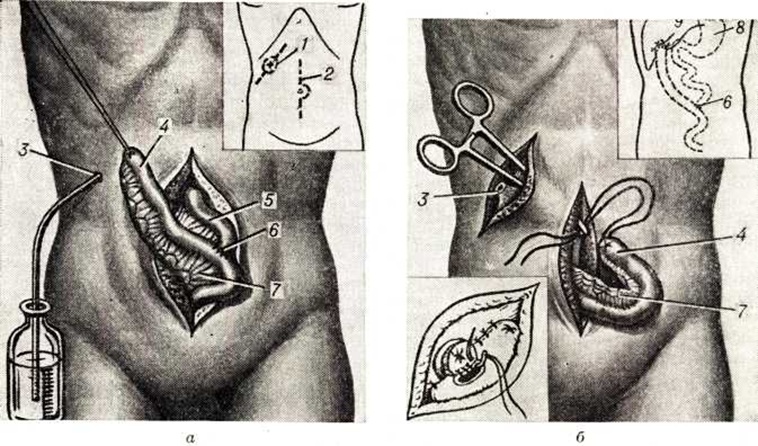

В ряде случаев наложение внутрибрюшинных анастомозов желчных протоков с пищеварительным каналом с целью ликвидации наружных Жёлчные свищи становится абсолютно невыполнимым, и тогда у больных со стойкими полными наружными Жёлчные свищи производят подкожную холефистулоэнтеростомию по методу Смирнова (рисунок 2).

Техника операции. Из верхней срединной лапаротомии производится мобилизация участка тощей кишки длиной в 35—40 сантиметров с сохранением питающих сосудов Мобилизованная петля пересекается и проводится через подготовленный подкожный туннель по направлению к Жёлчные свищи. Накладывается подкожный анастомоз по типу конец в бок между отсепарованным свищевым ходом и свободным участком тонкой кишки. Непрерывность кишечника восстанавливается анастомозом конец в бок между оральным отделом тощей кишки и свободным участком её.